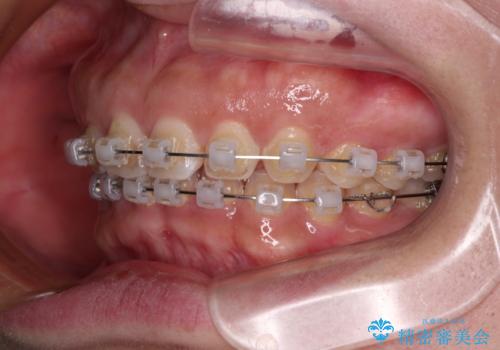

【モニター】ディープバイトを治す ワイヤー装置による矯正治療

- クリアブラケット

- 顎が疲れるほどのディープバイトを気にして来院された患者様です。

手前に傾斜している奥歯を直立させながら、歯列全体の平面を均一に整えることでディープバイトを改善していくこととしました。

ディープバイトは咬合力が強いことが特徴であり、より良い仕上がりとするために、臼歯部のコントロールを行いやすいワイヤー装置を用いて矯正治療を行うこととしました。